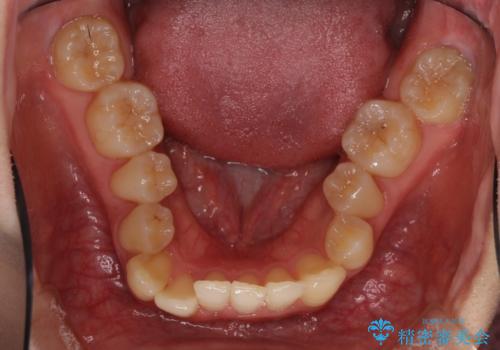

- 奥歯の反対咬合を気にして来院された患者様です。

反対咬合は上顎骨の幅が下顎骨よりも小さいことが原因なので、拡大装置により骨幅を広げて上下関係を改善し、その後インビザラインにて歯並びを整えることとしました。

反対咬合が改善され、食いしばり癖もなくなり、顎関節の負担が軽減されました。

上顎骨を拡大したことで前歯に隙間ができ、1ヶ月ほど恥ずかしい時期がありましたが、しっかりとした咬み合わせに仕上がり、患者様には大変満足していただきました。